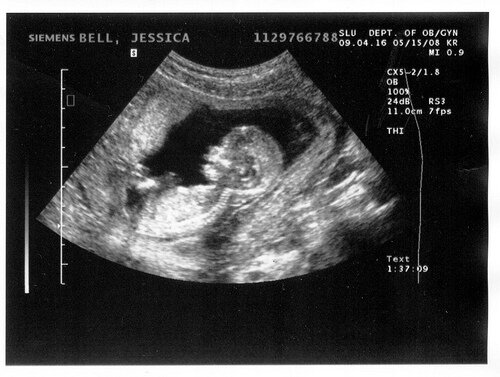

160 ударов в минуту или Первое УЗИ

Что такое первое УЗИ? Вы уже знаете, что у вас будет малыш. Но он там в животике такой маленький, меньше маленького орешка. Он вроде и есть, а вроде и нет. А на УЗИ можно услышать, как быстро-быстро бьется его маленькое сердце, и тогда только понимаешь, что там во всю уже идет новая жизнь. Что это не просто выдумка, что в животике мамы живет самый настоящий живой человек. И сердце его будет биться еще 9 месяцев со скоростью 160 ударов в минуту. Почти 3 удара в секунду!

Планово УЗИ делают три раза: на 10-12, на 20-22 и 30-32 неделях. Самое первое УЗИ можно сделать уже после 4 недели. Некоторые отмечают, что УЗИ может стать стрессовым фактором и помешать нормальному развитию ребенка. Есть разные технологии ультразвуховых исследований: 2D, 3D, 4D. Врачи говорят, что УЗИ абсолютно безопасно для плода, но на ранних сроках всё же сами советую делать простое 2D исследование.